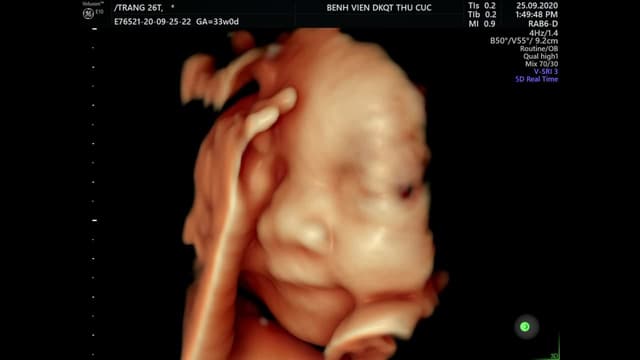

Siêu âm tuần 22 – Thời điểm vàng khảo sát dị tật thai nhi

Siêu âm tuần 22 là một trong những mốc siêu âm quan trọng mẹ không thể bỏ qua giúp mẹ tầm soát những dị tật thai nhi và những bất thường về bánh rau, nước ối ngay từ giai đoạn sớm. 1. Vai trò của siêu âm thai tuần 22 Siêu âm tuần 22 có […]